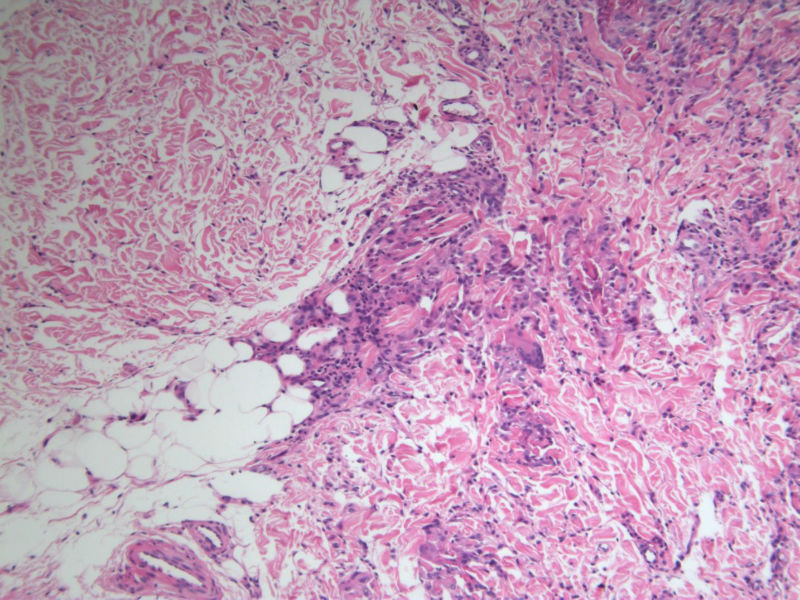

患者 男,8岁,双小腿渐粗红肿伴痒20余天,皮疹渐扩大,且出现硬化萎缩,入院后发现肺吸虫(+)。临床考虑:肺吸虫病硬皮病。请问斑竹大人考虑啥?

• 双小腿红肿伴痒20余天图3

图3

肺吸虫引起的嗜酸性粒细胞增多性疾病

肉芽肿中央不是凝固性坏死,好像是胶原纤维,否为环状肉芽肿或类脂质渐进性坏死

要考虑Wells综合征,依据有肺吸虫检查阳性、皮疹表现为肉芽肿样表现,可见到火焰征,不知道临床上血液分析检查结果如何,以及其他的检查结果怎么样?

肺吸虫皮下结节表现为肉芽肿炎症,这里的图片所显示的就是真皮及皮下组织的肉芽肿炎症,若是肺吸虫所致,按理是多少能见到嗜酸粒细胞的,但这里确实是没有看到,也没见可以的虫体征象,是没切到?也似乎没见很明显的硬皮病相关表现。

补充(临床医生邮件提供)该病人是一个8岁的小男孩,此次就诊主因双小腿肿胀发硬伴痒20天入院。既往体健,无内脏疾病史,入院时无发热、咳嗽、咳痰,无腹痛、腹泻等不适。专科检查:双小腿弥漫肿胀性褐色斑块,皮疹边界清楚,左小腿较右小腿肿胀明显,左小腿皮肤弹性较正常差,皮温正常,皮肤表面未见抓痕,未见红斑、丘疹、结节等,未见糜烂、破溃。入院查血分析嗜酸性粒细胞百分之六十多,余未见明显异常;体液免疫是IgE升高明显,有一百多倍吧,具体记不清。行肺吸虫皮试阳性,胸部CT及全腹CT检查均可见感染性病变,颅脑CT未见异常。给予杀虫治疗1疗程后,左小腿肿胀明显消退,现两小腿粗细相当,左小腿肿胀发硬也明显缓解,但褐色色沉一直未见明显消退,而且还向大腿蔓延,未见明显肿胀发硬的改变。患者现无瘙痒、肿胀感等不适。患者皮疹并不是肺吸虫病的典型皮疹,故行病理检查明确皮疹是否于肺吸虫病相关。

谢谢!开了眼界了!再次细看病理图,那些类似于“火焰征”的还真是像脱颗粒的嗜酸粒细胞,只是显而易见的嗜酸粒细胞不多见。末梢血嗜酸粒细胞那么多···推想皮疹应该是和肺吸虫有关,只是我们这辈的没啥见过、也很难见到了,还请前辈多多指点啊!

1、患者的皮损与血液中嗜酸性粒细胞增多有关,病理改变的确类似Wells综合征的灶状坏死,但没有特异性。

2、嗜酸性粒细胞增多可以表现为毛囊炎,蜂窝织炎,脂膜炎,筋膜炎,嗜酸性皮病和增多综合征等,

3、其产生的原因常常是寄生虫,此例明确有肺吸虫。所以两者有明确的相关性。